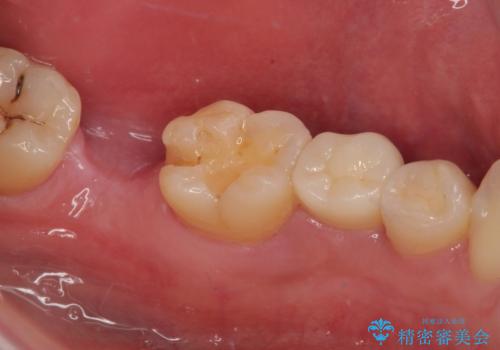

拡大鏡視野下で、コンポジットレジン、虫歯の除去を行い、フルジルコニアクラウン、セラミックインレーに適した形に整えました。

歯と歯茎の間に圧排糸と言われる糸を入れてシリコーン印象材にて精密な型どりをしました。

セラミックインレーの装着時には、唾液の侵入を防ぐために、ラバーダム防湿を行いました。